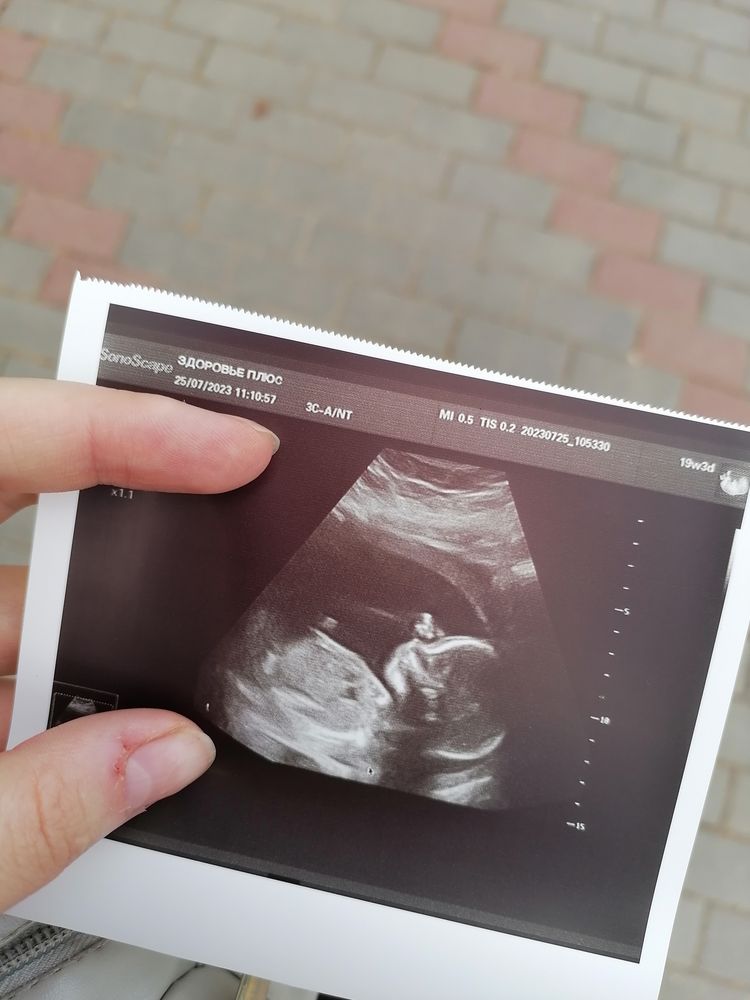

2й скрининг

Просто срез не посередине, а чуть в стороне от середины.

Эти снимки с узи🤣 Они же могут неправильно ловить изображение Лучше 3д делать

Все в порядке, видела много таких профилей. Вам правильно ниже написали, скорей всего срез не по средней линии

Врач говорит - отеки же еще У нас на таких кадрах также, а на 3д все нормально 😄

Не вижу ничего критичного Губа как губа Может в этот момент как раз ребенок воды околоплодные пил Может просто такое строение Вот нашла тоже со 2 скрининга фотку Изображение

Ну или возможно что в ребенка просто очень узкая верхняя губа, у вас с мужем какие губы ?

Валерия, врач ничего не сказала, а потом сколько ходила на узи то все время малышка отворачивается У меня тонкие, у мужа нет)

Сходите на 3д или 4д узи Врач вам ничего не сказал по этому поводу ? Может просто кадр не удачный